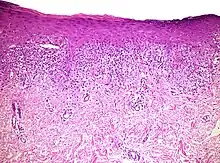

| Urticaria, lymphocyte predominant | Perivascular location. Mast cells are relatively sparse, potentially demonstrated with special stains, preferably tryptase stain. Extravasated erythrocytes are present in about 50% of the cases. No vasculitis.[14] | Dermal edema [solid arrows in (A,B)] and a sparse superficial predominantly perivascular and interstitial infiltrate of lymphocytes and eosinophils without signs of vasculitis (dashed arrow).[15] |

| Urticaria, lymphocyte predominant | Perivascular location. Mast cells are relatively sparse, potentially demonstrated with special stains, preferably tryptase stain. Extravasated erythrocytes are present in about 50% of the cases. No vasculitis.[14] | Dermal edema (solid arrows) and a sparse superficial predominantly perivascular and interstitial infiltrate of lymphocytes and eosinophils (dashed arrow) |